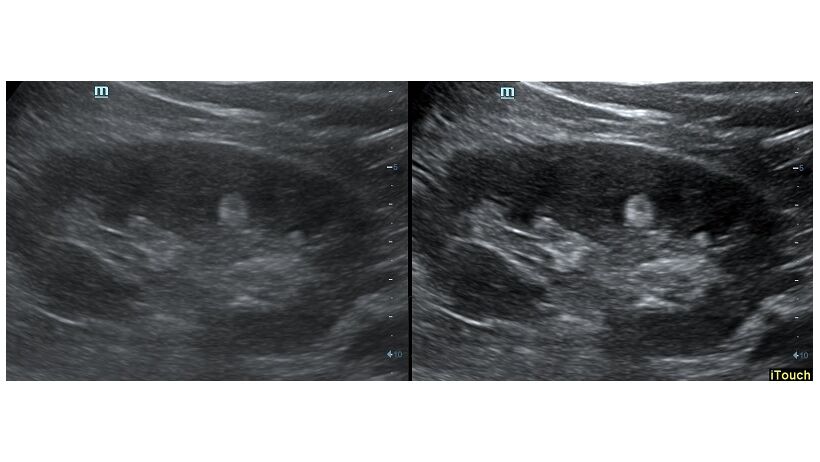

Обзор функции УЗИ: iTouch - автоматическая оптимизация изображения

Оптимизация изображения происходит и за счет постобработки. Наиболее часто используемый инструмент - общее усиление (Gain). Усиление делает изображение «ярче», но чем сильнее усиление, тем меньше различия между структурами. Также используются усиление по времени (TGC) и усиление по длине (LGC), которые позволяют изменять отображение на экране послойно, позволяя подсветить гипоэхогенные участки, или, наоборот, снизить визуально эхогенность слишком ярких моментов. Данный вид оптимизации требует много времени, для упрощения работы доктора на приборах Mindray внедрена система автоматической оптимизации - iTouch.